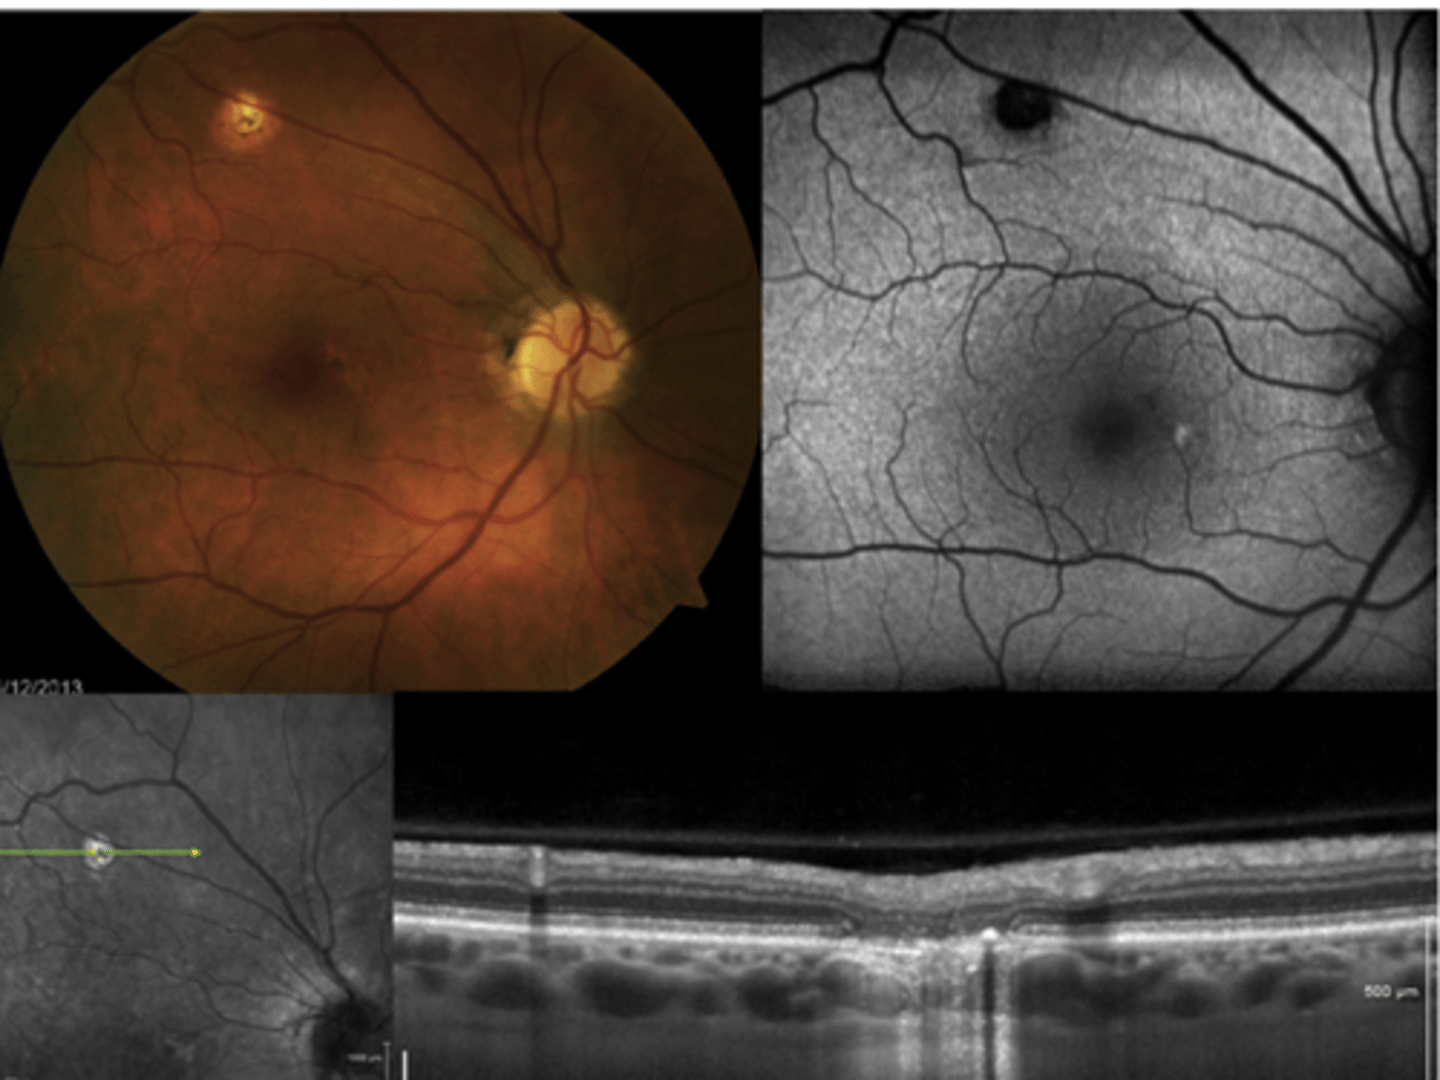

How does choroidal rupture appear on OCT here?

loss of RPE continuity at site of rupture = inner choroid atrophy

How does choroidal rupture appear on OCT here?

RPE disruption

+/- hemorrhage

How does choroidal rupture appear on FAF?

hypoAF where RPE is atrophied